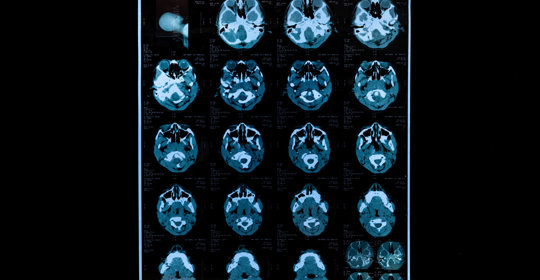

腦血管瘤的發生與年齡、是否有基礎病如高血壓、糖尿病等因素有關。若患者有胸痛、呼吸困難、心悸、暈厥或咳血等症狀,則需緊急評估和治療。